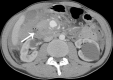

Presentation of case: A 62-year-old man with a two-day history of epigastric pain was admitted at emergency department. CT showed a retroperitoneal haematoma due to a 1.5cm posterior inferior PDA ruptured aneurysm. Angiography had been conducted immediately: both inflow and outflow of the aneurysm were embolized. Another CT scan had been conducted, which revealed residual flow inside the aneurysm sac fed by small collateral vessels. Sub-selective catheterization was repeated and definitive haemostasis was obtained by embolizing the collateral vessels. Postoperative course was uneventful. CT scan follow-up at 36 months showed no abnormalities.